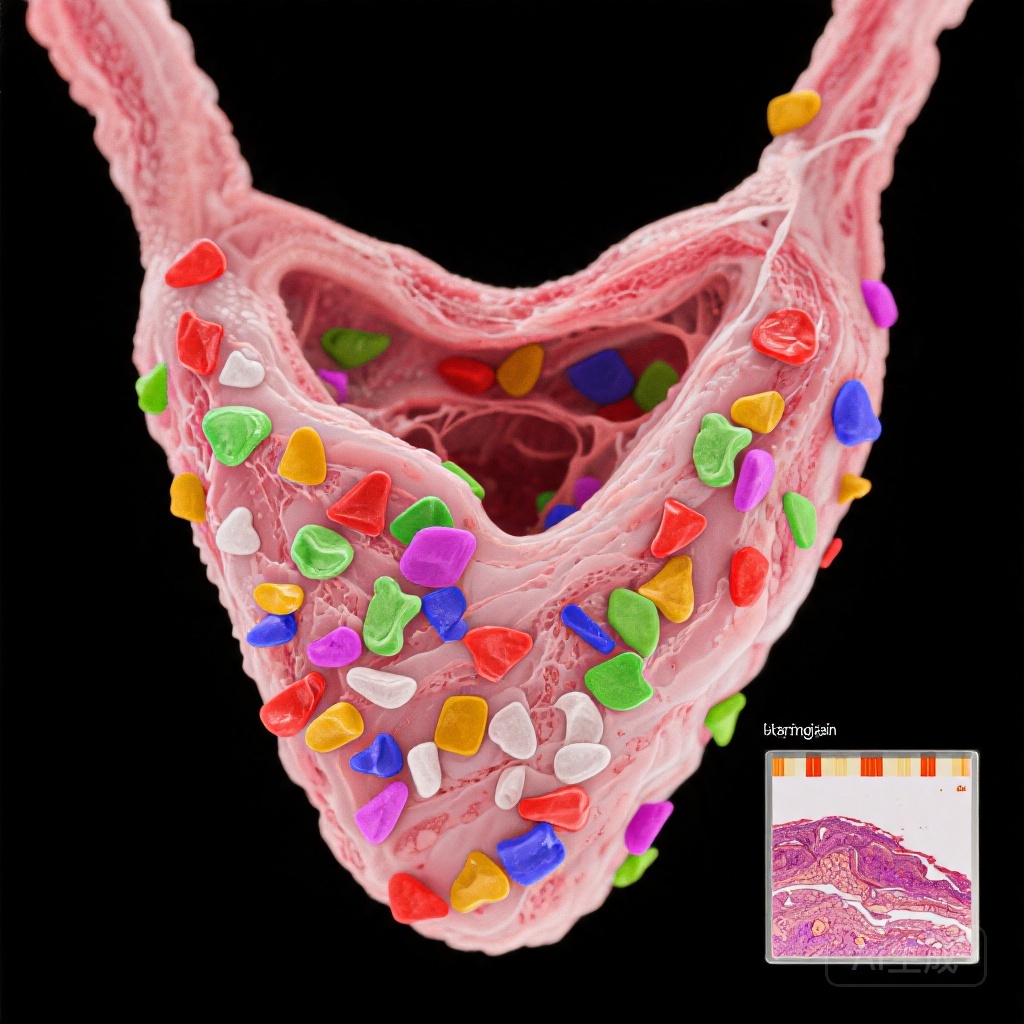

Nghiên cứu này so sánh mô tuyến giáp từ 29 bệnh nhân AIT được xác nhận qua hình ảnh học và 29 đối chứng cùng độ tuổi và giới tính có u tuyến giáp lành tính. MPs được định lượng bằng phương pháp nhiệt phân-gas sắc ký-chromatography-mass spectrometry (Py-GC/MS) và đặc trưng thông qua vi quang phổ Raman và vi kính điện tử quét (SEM).

Tổng nồng độ MPs đáng kể cao hơn ở bệnh nhân AIT (trung vị: 19,9 μg/g so với 1,9 μg/g; p=0,012), với PVC là polyme chiếm ưu thế. Vi quang phổ Raman cho thấy số lượng MPs cao hơn trong mô AIT (172 so với 50,2 đơn vị/g, p=0,037), với kích thước hạt từ 33,9 đến 1467 µm. Đặc điểm hình thái (kích thước, hình dạng, màu sắc) không khác biệt giữa các nhóm.